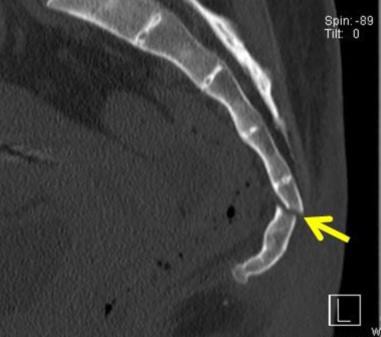

(3)第一、二尾椎骨折:如圖五

(4)第二三尾椎骨折:圖六